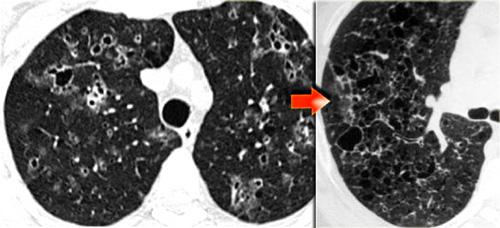

Bệnh nhân này nhập viện với triệu chứng khó thở cấp tính và phim X-quang ngực bình thường (không trình bày).

HRCT lúc nhập viện (trái) cho thấy các vùng kính mờ theo phân bố tiểu thùy.

HRCT kiểm tra mười ngày sau (phải) cho thấy các tổn thương đã thoái lui hoàn toàn mà không cần điều trị.

Các tổn thương được cho là do viêm phổi quá mẫn.